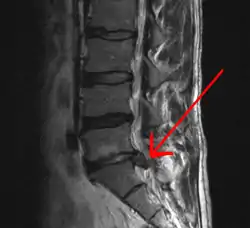

Imaging is indicated when there are red flags, ongoing neurological symptoms that do not resolve, or ongoing or worsening pain.[5] In particular, early use of imaging (either MRI or CT) is recommended for suspected cancer, infection, or cauda equina syndrome.[5] MRI is slightly better than CT for identifying disc disease; the two technologies are equally useful for diagnosing spinal stenosis.[5] Only a few physical diagnostic tests are helpful.[5] The straight leg raise test is almost always positive in those with disc herniation,[5] and lumbar provocative discography may be useful to identify a specific disc causing pain in those with chronic high levels of low back pain.[45] Therapeutic procedures such as nerve blocks can also be used to determine a specific source of pain.[5] Some evidence supports the use of facet joint injections, transforminal epidural injections and sacroiliac injections as diagnostic tests.[5] Most other physical tests, such as evaluating for scoliosis, muscle weakness or wasting, and impaired reflexes, are of little use.[5]